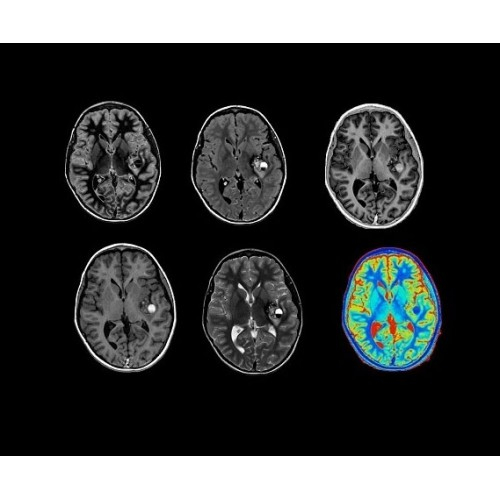

• Специальный пакет приложений для измерения и сравнения объемных изображений ЦНС с нормами поможет вам в диагностике нейродегенеративных заболеваний, а дополнительные инструменты визуализации — в постановке точного диагноза с помощью бета-амилоидов и радиоизотопных маркеров ФДГ.